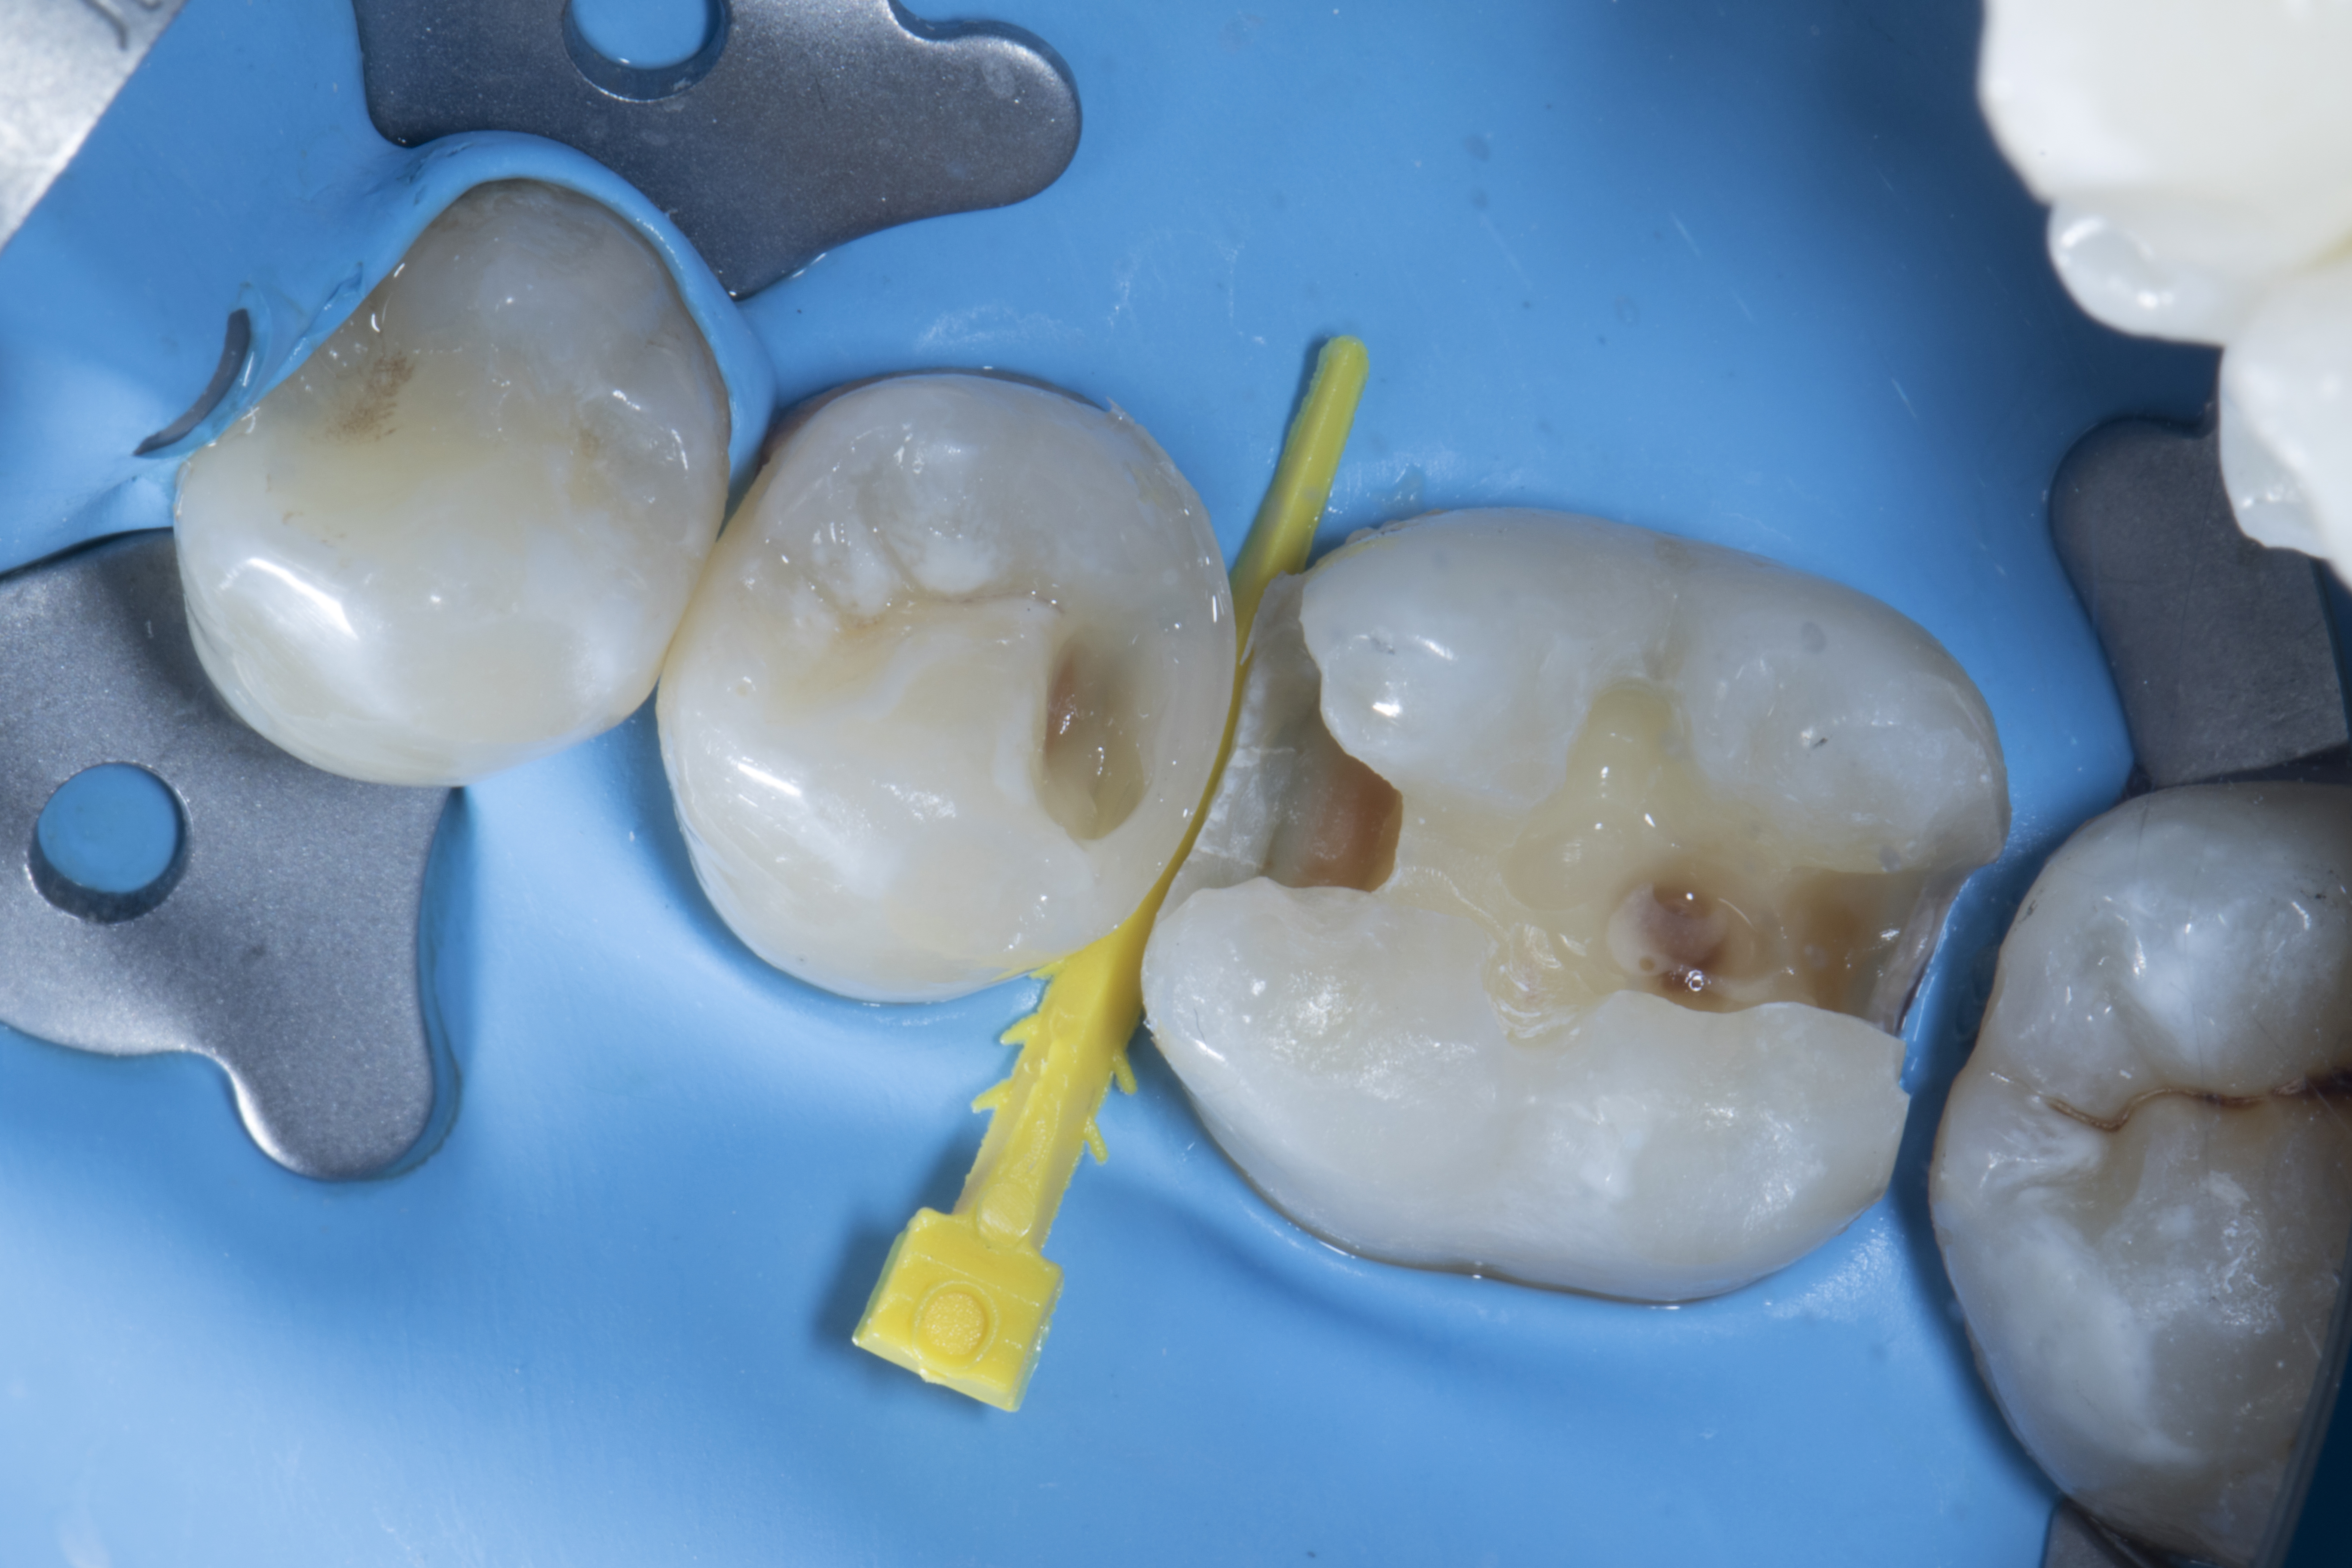

Step 8 - Restoration of  tooth #36. A tall molar FX300 (blue) band selected for mesial and FX150 (red) band selected for the distal-proximal box. The bands were stabilized with extra small (yellow) and small (blue) Fusion Wedges respectively. The bands were selected as per the height of the proximal box on each side. The tab on the marginal aspect of the FX300 band was bent over the adjacent tooth so that the height of the proximal wall is known. The FX400 (blue, short) ring was placed and the proximal wall / mesial contact built up with composite the same as described earlier in Step 5.

Figure 7

Figure 7. A tall molar FX300 (green) band was selected for mesial and FX150 (red) band for the distal-proximal box. Both bands were stabilized with extra small (yellow) and small (blue) Fusion Wedges respectively. Then a FX400 (blue, short) ring was placed and the proximal wall / mesial contact was built up.

Step 9 - Making distal contact with the FX500 (orange, tall) ring was described in step 5.

Figure 8

Figure 8. Making distal contact with a FX500 (orange, tall) ring.

Step 10 – After removal of all rings and bands the resulting Class I cavity was filled with composite (Shofu Beautifil II LS) in small increments to avoid C factor, while mimicking natural anatomy. Brown stains were added to give a natural effect.

Figure 9

Figure 10

Figure 9. After removal of all rings and bands, the resulting Class I restoration is now ready for filling.Figure 10. The cavity was filled with composite Beautifil II LS (Shofu) in small increments to avoid C factor, while mimicking natural anatomy. Brown stains were added to give a natural effect.